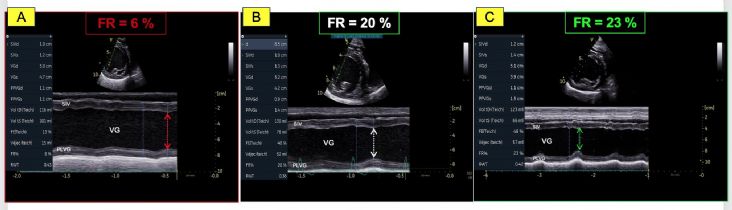

- La valeur très diminuée de la fraction de raccourcissement (FR) égale à 6 %; (valeurs usuelles (VU) 29%) (Figure 1A) ainsi que de la fraction d'éjection (FE) ventriculaire gauche égale à 16% ; (VU 42%) (Figures 2A et 2B) ;

- Une dysfonction systolique nettement améliorée avec une fraction d'éjection normalisée à J0 + 9 mois (Figures 2E et 2F, Tableau 2) malgré la persistance d'une hypokinésie radiale du septum interventriculaire qui contribue au maintien d'une fraction de raccourcissement diminuée mais de façon moindre (FR égale à 23 % à J0 +

9 mois versus 20% à J0+ 3 mois versus 6 % à J0 (Figures 1B, 1C et Tableau 2) ;

- Une diminution marquée en systole du volume et du diamètre ventriculaire gauche, lesquels restent néanmoins augmentés (Tableau 2 et Figures 1B et 1C versus 1A) ;